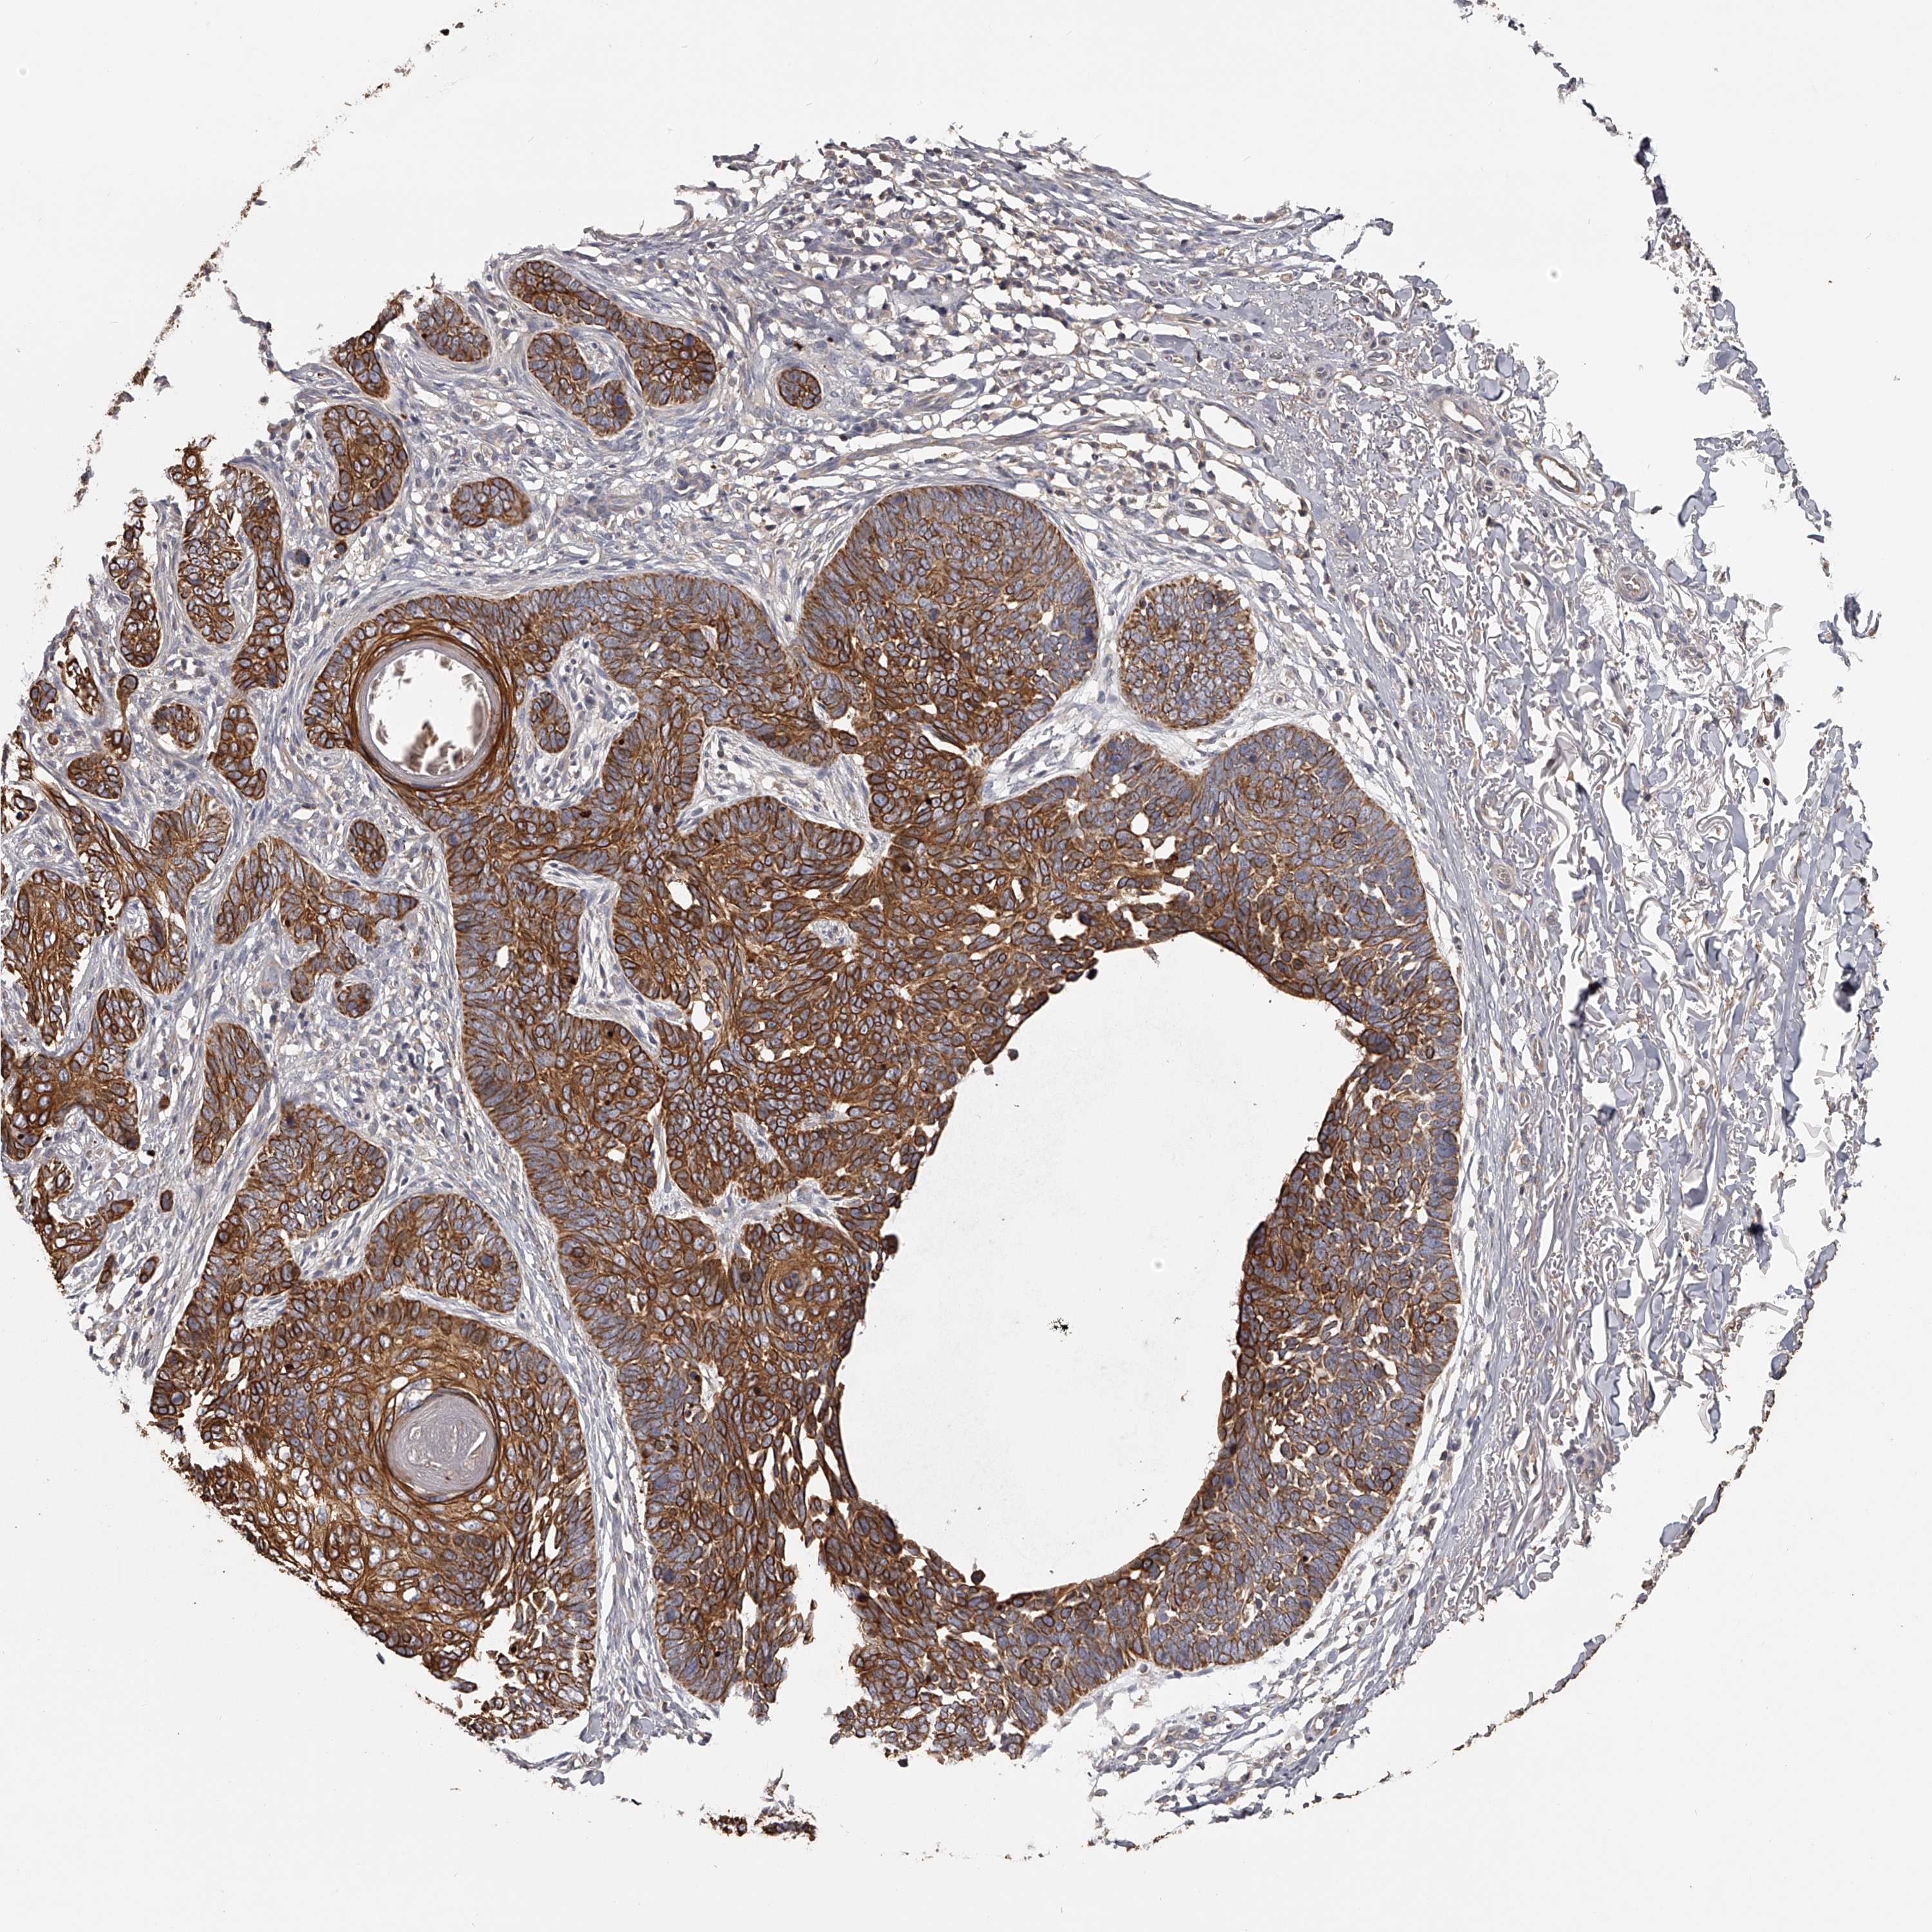

SKIN CANCER - Protein expressioni

A mouse-over function shows sample information and annotation data. Click on an image to view it in a full screen mode. Samples can be filtered based on level of antibody staining by selecting one or several of the following categories: high, medium, low and not detected. The assay and annotation is described here.

Antibody stainingi

Antibody staining in the annotated cell types in the current human tissue is reported as not detected, low, medium, or high, based on conventional immunohistochemistry profiling in selected tissues. This score is based on the combination of the staining intensity and fraction of stained cells.

Each image is clickable and will lead to virtual microscopy that enables deeper exploration of all samples and also displays staining intensity scores, fraction scores and subcellular localization as well as patient and tissue information for each sample.

Antibody HPA026726

Antibody HPA026764

Antibody CAB010907

Staining

High

Medium

Low

Not detected

Basal cell carcinoma